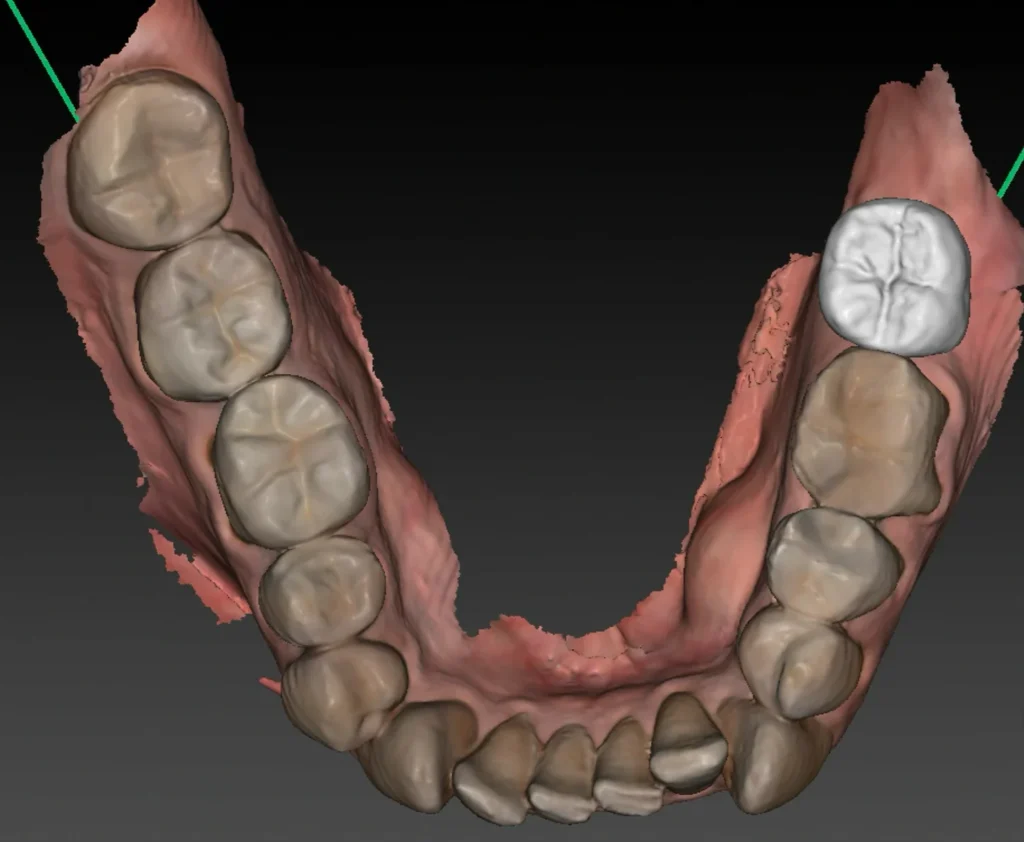

Une empreinte optique est également effectuée. Elle permet :

- de visualiser avec précision le relief gingival et d’identifier les zones nécessitant éventuellement une greffe de gencive ;

- d’évaluer les rapports occlusaux en vue de la future restauration prothétique ;

- d’alimenter la planification numérique en superposant les données optiques au volume osseux issu du Cone Beam.

L’ensemble de ces données permet ensuite de réaliser une planification implantaire précise, fondée sur une analyse tridimensionnelle croisée des tissus durs et mous, et tenant compte des exigences prothétiques.

Une fois l’ostéointégration confirmée, la phase prothétique peut débuter. Cette étape consiste à réaliser la ou les couronnes implantaires qui viendront se fixer sur les implants intégrés dans l’os.

La première étape consiste à prendre une empreinte optique ou physique de la zone afin de modéliser avec précision la position de l’implant, la forme de la gencive et l’occlusion. La technique d’empreinte optique, réalisée sans matériau de moulage, est plus confortable pour le patient et permet une transmission numérique directe au laboratoire, accélérant ainsi les délais de fabrication prothétique.